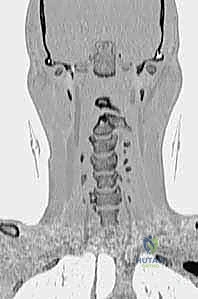

- التصوير المقطعي المحوسب (CT Scan) ثلاثي الأبعاد: وهو الفحص الأهم لتخطيط الجراحة. يعطي الدكتور هطيف خريطة دقيقة لتشريح العظام، حجم الكتل المفصلية، ومسار الشريان الفقري، مما يسمح له باختيار حجم ومسار المسامير بدقة المليمتر.

- التصوير بالرنين المغناطيسي (MRI): ضروري لتقييم حالة الحبل الشوكي، وجود أي كدمات أو تلف داخله، وتقييم حالة الأربطة (خاصة الرباط المستعرض).